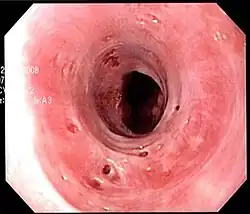

Endoscopic image of esophageal intramural pseudodiverticulosis demonstrating the flask-like outpouchings of the esophageal wall. | |

Esophageal intramucosal pseudodiverticulosis is typically diagnosed at the time of endoscopy of the esophagus. Endoscopy shows evidence of the pseudodiverticulae, which are typically numerous, appear like pits in the wall, and may be preferentially located in the upper esophagus.[3][5] The mucosal lining of the esophagus may be inflamed, and this can be seen on endoscopy or biopsy; the mucosa, however, may also be normal if esophagitis is not the cause of the pseudodiverticulosis. The condition must also be excluded from esophageal cancer, which may be done at the time of endoscopy, or which may require esophageal biopsy.[3]